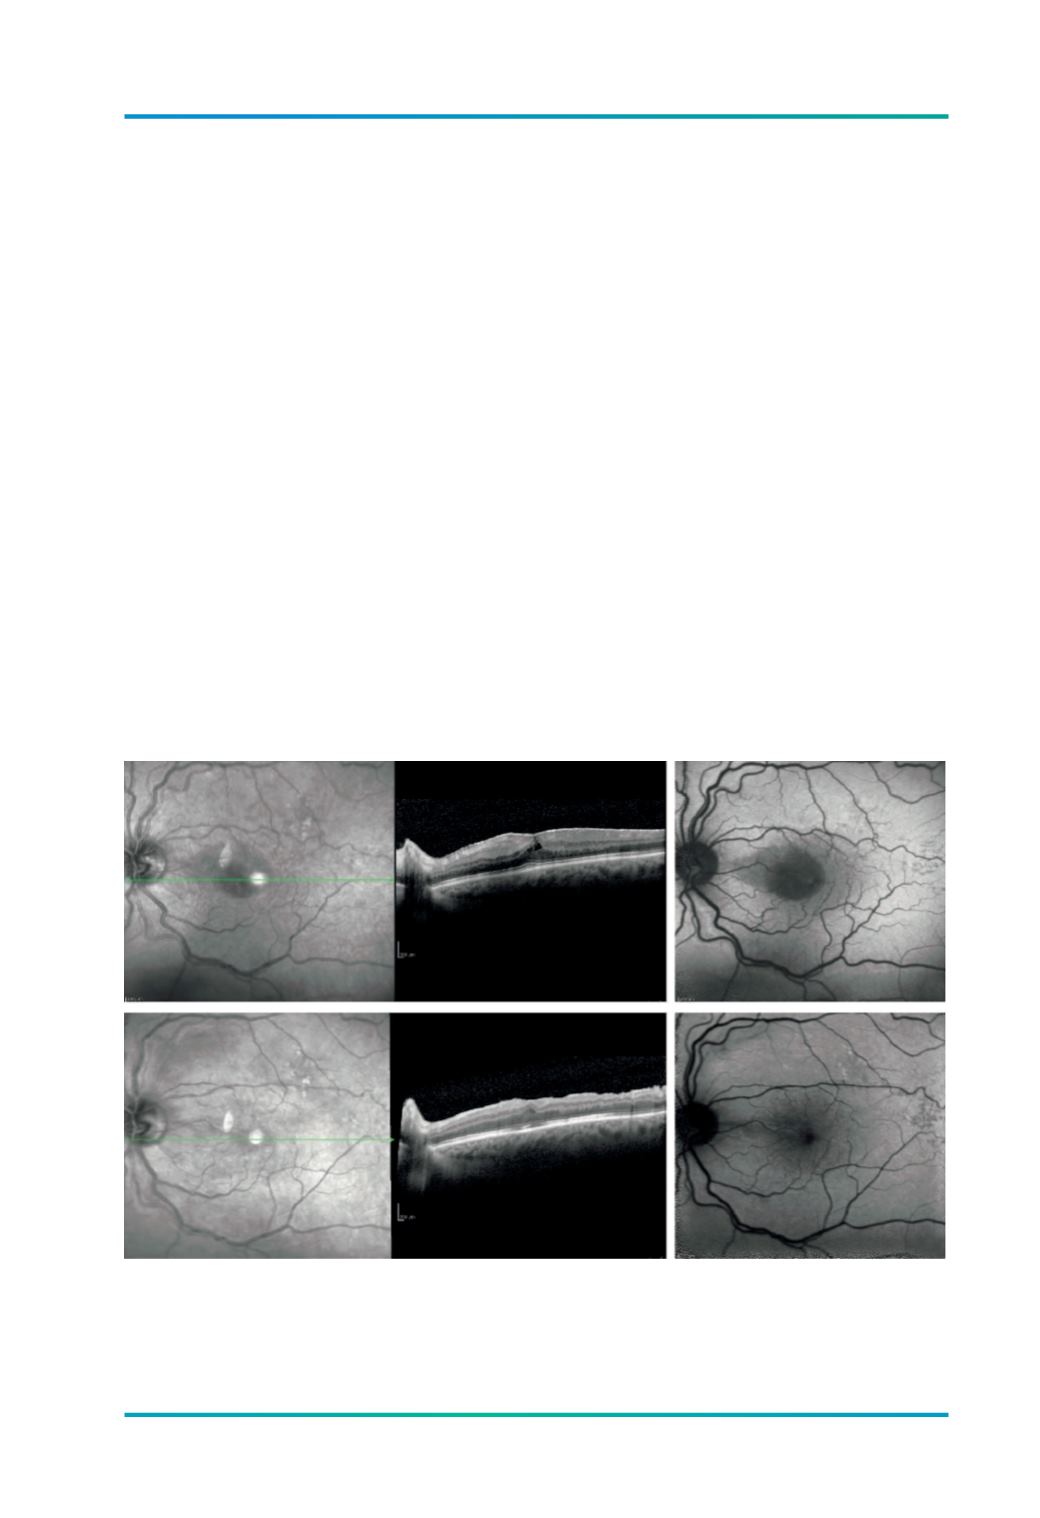

Figura 2.

A pré-operatório- CT com membrana epirretiniana condicionando um edema traccional da retina onde

são evidentes interrupções na MLE no feixe papilo-macular; AV 3/10. B) Hipo-autofluorescência na região

macular central e feixe papilo-macular secundária à presença da MER. C) pós-operatório - OCT 3 meses

após extracção da MER. D )recuperação quase total da normal auto-fluorescência macular; AV 6/10.

A

B

C

D